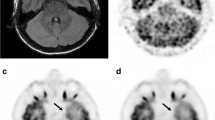

Representative sections of 18F-FDG PET, fused PET/3D-FLAIR, and 3D-FLAIR images are shown in Fig. 3 and supplementary Fig. 3.

Individual 3D-FLAIR image (first row) and 18F-FDG PET images with OSEM + TOF + PSF reconstruction (second to fifth rows) in a representative participant. On the individual 18F-FDG PET image with OSEM iteration 64 + TOF + PSF (fourth row), FDG uptake can be clearly distinguished (good) in all structures, including the inferior olivary nuclei (ION, a), dentate nuclei (DN, b), midbrain raphe nuclei (MRN, c), inferior colliculi (IC, d), mammillary bodies (MB, e), red nuclei (RN, f), subthalamic nuclei (STN, g), lateral geniculate nuclei (LGN, h), medial geniculate nuclei (MGN, i), and superior colliculi (SC, j). On iteration 16 (third row), 18F-FDG accumulation can be clearly seen (good) in the DN (b), IC (d), RN (f), STN (g), and SC (j); and is obscure (fair) in the ION (a), MRN (c), MB (e), LGN (h), and MGN (i). On iteration 256 (fifth row), FDG uptake is good in the ION (a), DN (b), IC (d), MB (e), and SC (j); and fair in the MRN (c), RN (f), STN (g), LGN (h), and MGN (i). On iteration 4 (second row), 18F-FDG accumulation is fair in the DN (b), IC (d), and RN (f); and cannot be distinguished with surrounding uptake (poor) in other structures, including the ION (a), MRN (c), MB (e), STN (g), LGN (h), MGN (i), and SC (j)